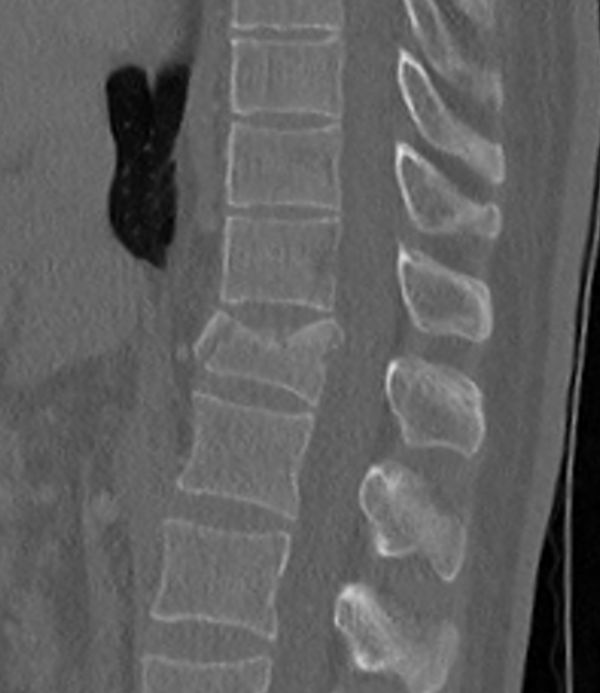

• Tříštivá zlomenina obratle T12 po kombinovaném ošetření vnitřním fixátorem v rozsahu T11-L1